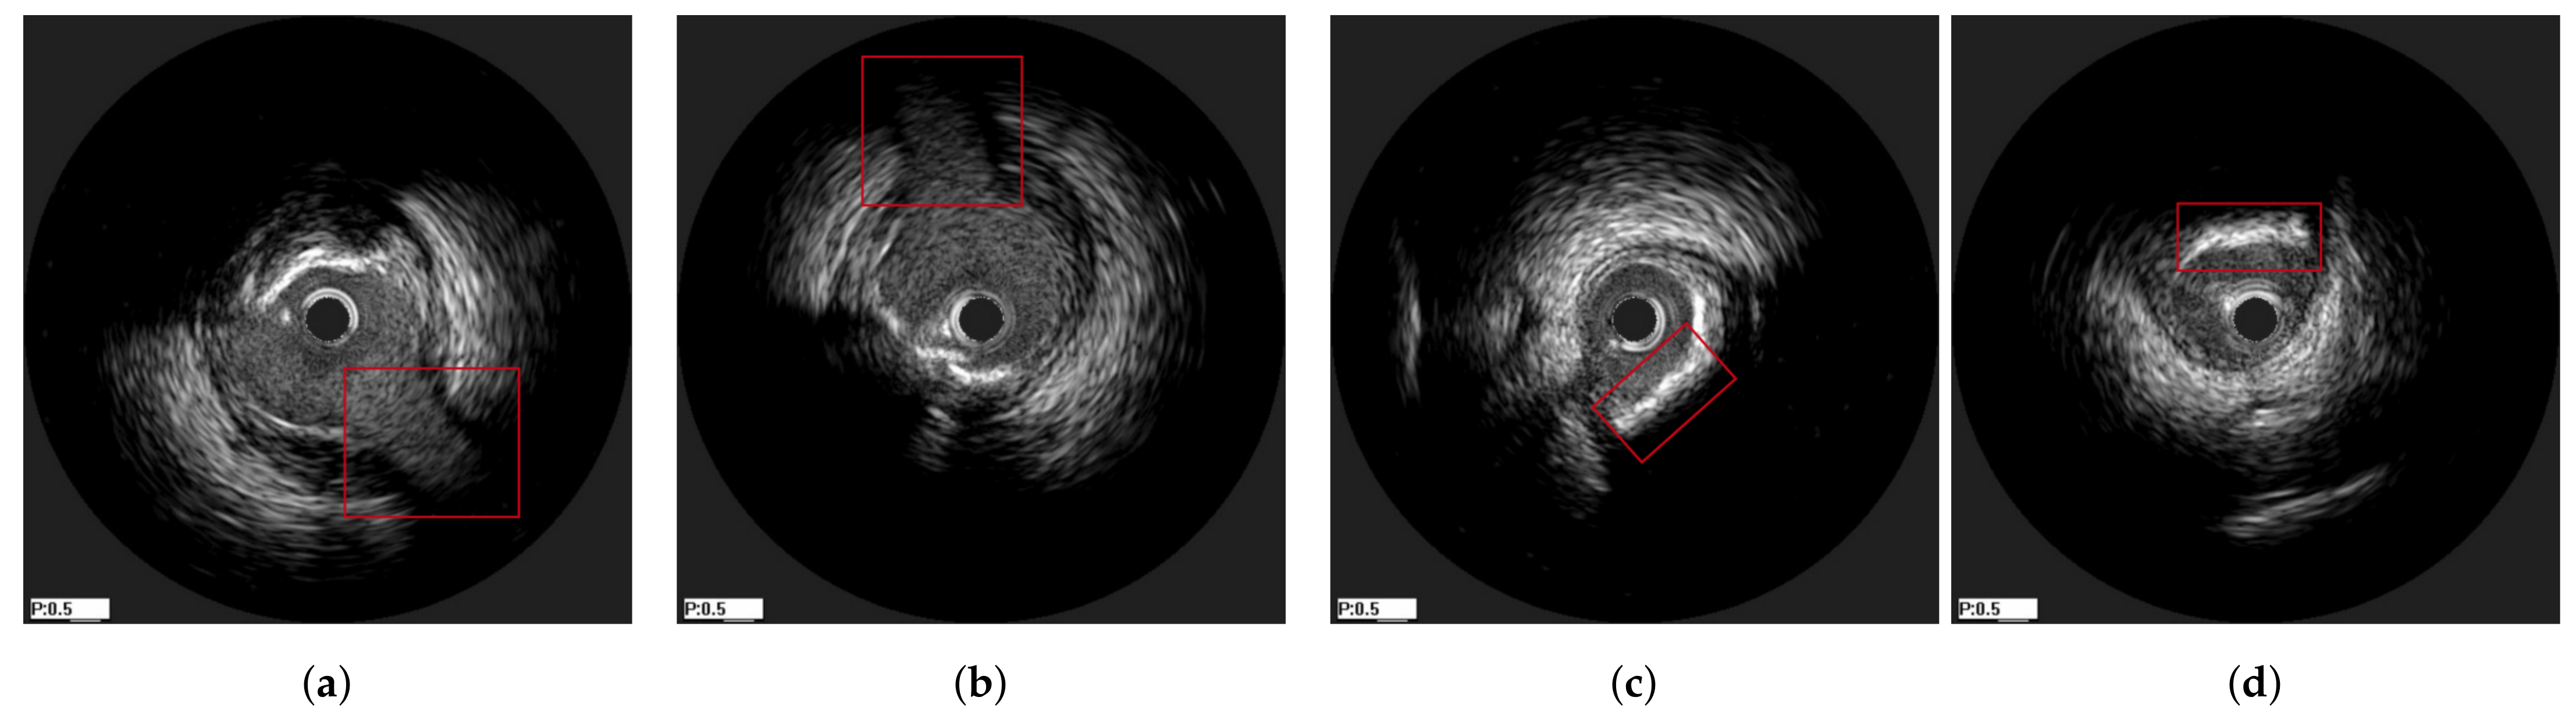

In Figure 10, an explanatory result of the axial registration step following longitudinal registration for a pair of IVUS images of the two pullbacks is presented. Figure 10a,b present longitudinally registered frames of the first and second pullbacks of patient 6 (patient 18), respectively, while Figure 10c is the result of the axial registration between (a) and (b). Two other similar examples are depicted in Figure 11 and Figure 12. The result showed that the images were further aligned and the anatomical correspondence of the vessels structures was improved. The match was not perfect due to the existence of non-linear changes in the vessels such as extension of the vessel after stent deployment or increase of the size of the plaque, which could not be fully aligned with rigid registration techniques. Another reason is that the end-diastolic matched pairs may not depict exactly the same area, but rather neighboring ones. The reason for using rigid registration was because we wanted to achieve an overall alignment of the frames without altering the actual shape of the vessel’s structures as a non-rigid deformation would do. To this end, the obtained results as highlighted in Figure 9, Figure 10, Figure 11 and Figure 12, demonstrated that the proposed registration framework was a fast and robust tool to establish a more intuitive comparison in temporal IVUS pairs.

Figure 10. The alignment of a bifurcation can be observed under the marked area. (a) a frame from the first pullback of patient 6, (b) its corresponding frame from the second pullback of patient 6, (c) the axially (2D) registered frame from Figure 10b with respect to Figure 10a.

Figure 11. The alignment of the landmarks can be observed under the marked areas. (a) a frame from the first pullback of patient 18, (b) its corresponding frame from the second pullback of patient 18, (c) the axially (2D) registered frame from Figure 11b with respect to Figure 11a.

Figure 12. The alignment of the landmarks can be observed under the marked areas. (a) a frame from the first pullback of patient 3, (b) its corresponding frame from the second pullback of patient 3, (c) the axially (2D) registered frame from Figure 12b with respect to Figure 12a.